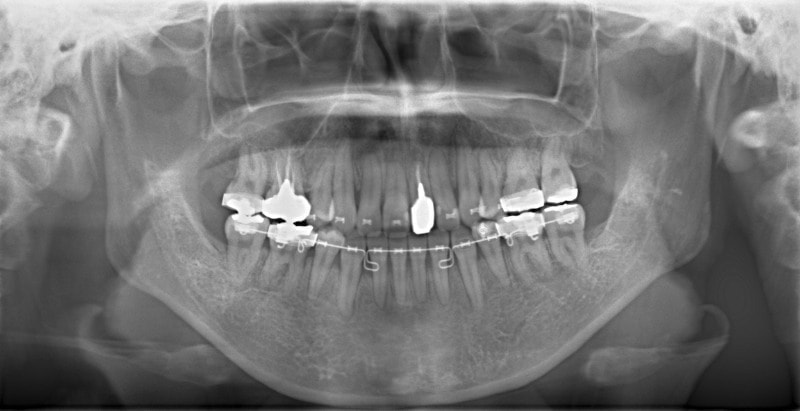

セファロ分析結果:上顎の劣成長と下顎の過成長が認められる値が出ています。重度の叢生といえます。

修復歯、補綴歯もあります。下顎8番が水平埋伏しています。

歯根のパラレリング(平行性)が獲得されております。

下顎8番は、両側抜歯済みです。

顎位は良好な状態です。